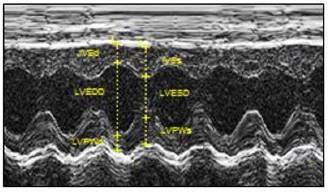

Figure 3

Echocardiographic evaluation of cardiac function. LPS was administered to neonatal rats, as described under Materials and Methods. The control rats received saline. At 6 weeks of age, transthoracic echocardiography was performed on the rats after they were anaesthetized with inhaled isoflurane, as described under Materials and Methods. A representative echocardiography shows the measurement of LVSd, LVEDd, LVPWd, LVSs, LVEDs, and LVPWs. A summary of the most relevant cardiac measurements was shown in Table 1. Data were analyzed by Student's t-test.

At 6 weeks of age, rats were then subjected to transthoracic echocardiography using the LOGIQ e Ultrasound (GE Medical System, Jiangsu) as previously described [20]. Briefly, the rat was shaved in the chest area, and a layer of acoustic-coupling gel was applied to the thorax. Then the rat was placed in the left lateral decubitus position. An M-mode recording of the LV was obtained at the level of the mitral valve in the parasternal view using two-dimensional (2D) echocardiographic guidance in both the short and long axis views. Cardiac function and heart dimensions were evaluated by 2D echocardiography on the anesthetized (2% isoflurane) rat. M-mode tracing was used to measure interventricular septal end diastole (IVSd), interventricular septal end systole (IVSs), posterior wall thickness at end diastole (LVPWd), and end systole (LVPWs). LV mass and functional parameters such as LV end-diastolic dimension (LVEDD), LV end-systolic dimension (LVESD), LV end-diastolic volume (LVEDV) and LV end-systolic volume (LVESV) were calculated using the above primary measurements and accompanying software. Left ventricular ejection fraction (EF) was calculated as (LVEDV-LVESV)/LVEDV and the percentage of left ventricular fractional shortening (FS) was calculated as (LVEDD-LVESD)/LVEDD. The echocardiography data was recorded and analyzed blinded to the different treatments.

The echocardiographic assessment on in vivo animals indicated that neonatal LPS exposure exhibited no effects on baseline heart function in both male and female rats at the age of 6 week-old (Figure 3 and Table 1). Consistent with the results of the echocardiographic analysis, the ex vivo baseline LV functions before ischemia were also not changed between the LPS-treated and saline control groups in both male and female rats in an isolated heart with Langendorff preparation (Table 2).